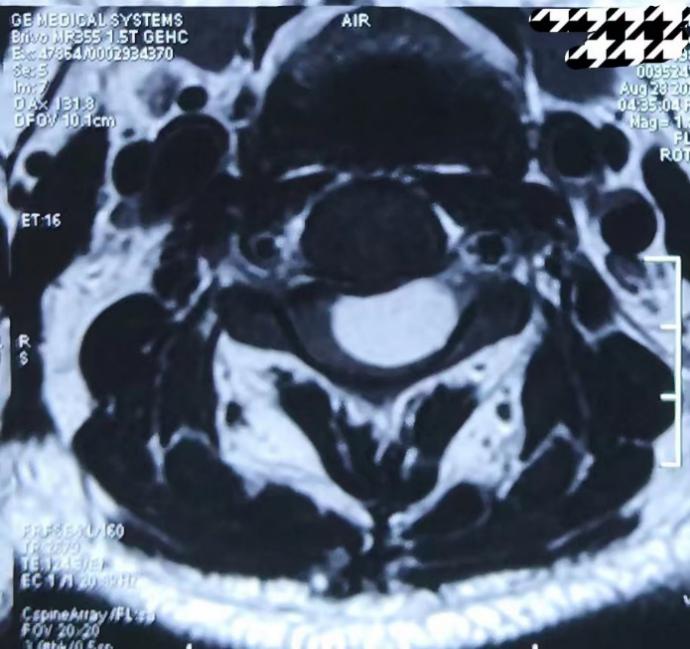

颈椎核磁轴位显示病变从前方将脊髓压成薄片状,呈脊髓嵌入征

为进一步诊治,杭女士辗转前来北京市垂杨柳医院神经外科寻求帮助。神经外科主任张锟带领全科医生就杭女士的病情展开讨论,认为患者慢性病程,逐渐加重,表现为颈神经根痛症状。颈椎核磁显示颈3-4水平椎管内脊髓外囊性病变,位于脊髓腹侧面,边界清楚,呈长T1长T2信号,脊髓明显受压变扁,打药后无强化。诊断考虑为良性囊性病变,肠源性囊肿可能性最大,为一种少见的先天性病变。手术指征明确,手术难点及风险在于,病变位于高颈髓水平且位于脊髓腹侧面,从后方入路显露病变时需牵拉脊髓及神经根,术后可能出现高位截瘫及呼吸困难。此外囊肿壁可能与脊髓黏连紧密,无法全切病变而导致复发。

多数肠源性囊肿MRI平扫表现为圆形、类圆形或椭圆形,与脊髓长轴一致,一般边界清楚,脊髓局部受压变扁。主要表现为长T1 信号、长T 2 信号,信号强度取决于其内容物的成分,如含较多蛋白质成分或囊内出血,增强扫描多数肠源性囊肿无强化效应,少数病例可见囊壁不均匀环状强化,可能与囊壁内含纤维、平滑肌或感染有关。